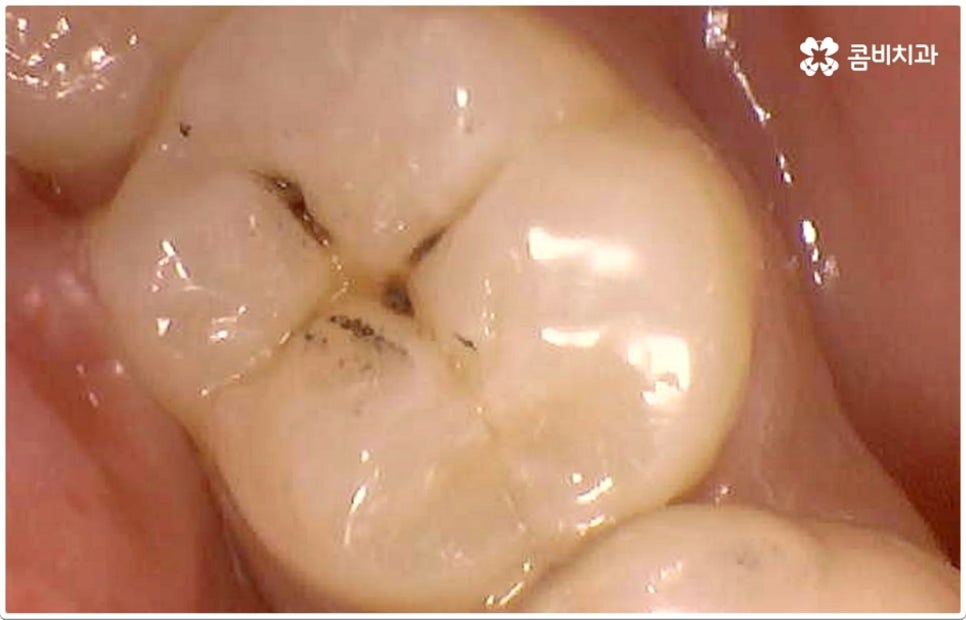

충치의 원인이 되는 세균이 급격하게 증식하게 되는 온상인 치석은 치아와 치아 사이, 또는 치아와 잇몸 사이에 플라그와 음식물 찌꺼기가 엉겨붙어 딱딱하게 굳은 것이라서 칫솔질로 제거되지 않기 때문에 주기적인 스케일링 치료를 통해 물리적으로 떼어낼 필요가 있어요. 또한 초기 충치 또는 치아사이충치 같은 경우 환자분들의 입장에서 바로 발견하는 것이 어려울 수 있기 때문에 혹시 자신이 모르는 사이에 충치가 진행되고 있지는 않은지 꼼꼼하게 살펴보고 빠르게 대처할 수 있도록 하기 위해 1년에 한 번 또는 두 번 정도 치과에 내원하셔서 정밀 검진을 받으시길 권유드리고 있습니다.

게다가 치아사이충치 는 두 치아의 인접면에 발생하여 한꺼번에 두 치아에 손상을 주기 때문에 보다 빠른 대처가 필요한데도 불구하고 말씀드린 것처럼 발견하기도 쉽지 않을 뿐더러 음식을 저작하는 치아의 교합면 (위아래 맞물리는 면) 에 생기는 충치가 아니기 때문에 수직으로 우식 부분까지 파고 내려가는 치과 충치 치료 기구들의 특성상 접근하기가 용이하지 않아 까다로운 진료에 속한다고 할 수 있어요. 특히 환자분들의 치아사이충치 발병 상황에 따라 치료 과정에서 부득이하게 삭제해야 하는 치아량이 생각보다 많아지는 케이스가 있을 수 있으므로 이에 대해 잘 알아두실 필요가 있습니다.